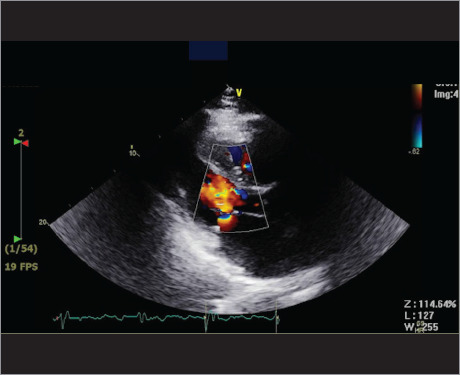

本案例研究探讨了一位80岁男性患者的历程,他有高血压、糖尿病、冠状动脉搭桥术后冠状动脉疾病、心房颤动和心力衰竭的病史。9个月前,因严重的二尖瓣返流,他接受了二尖瓣夹夹术。尽管最初有所改善,但患者再次出现症状,包括休息时呼吸困难和下肢水肿。本病例的结果-发现二尖瓣置换术的需要-为二尖瓣夹断并发症的管理提供了见解,并强调管理需要细致入微的方法。

This case study explores the journey of an 80-year-old male patient with a history of hypertension, diabetes, coronary artery disease after coronary artery bypass grafting, atrial fibrillation, and heart failure. Nine months before he presented to the emergency department, he had undergone mitral valve clipping for severe mitral valve regurgitation. Despite initial improvement, the patient experienced return of symptoms, including dyspnea at rest and lower limb edema. The results of this case-discovery of the need for mitral valve replacement-provides insights into the management of complications from mitral valve clipping and emphasizes that management requires a nuanced, meticulous approach.